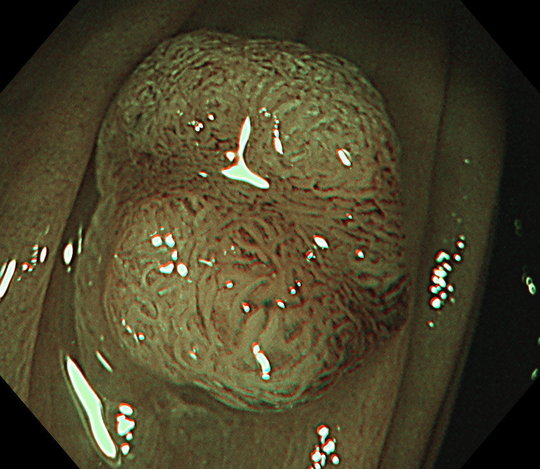

大腸内視鏡検査は発見と同時に大腸ポリープを治療することができる唯一の方法です。つまり大腸ポリープや転移の可能性のない早期のがんについて、検査と治療を一緒に行うことができます。このことが内視鏡検査の最大の特長といえるでしょう。

通常の光で病変を確認し、その後に特殊な光(狭帯域光、NBI: Narrow Band Imagingや色素を使用して腫瘍の表面の特徴から、病変が良性か悪性か、また浸潤(腫瘍の悪性度合い、転移のしやすさにも関係しています)の有無についても評価します。

病変を正しく診断できることが大腸内視鏡では非常に重要です。その正確な診断を行った上で、内視鏡検査の流れの中、腫瘍やポリープが見つかれば、そのままその病変を切除します。

実際の大腸ポリープ切除